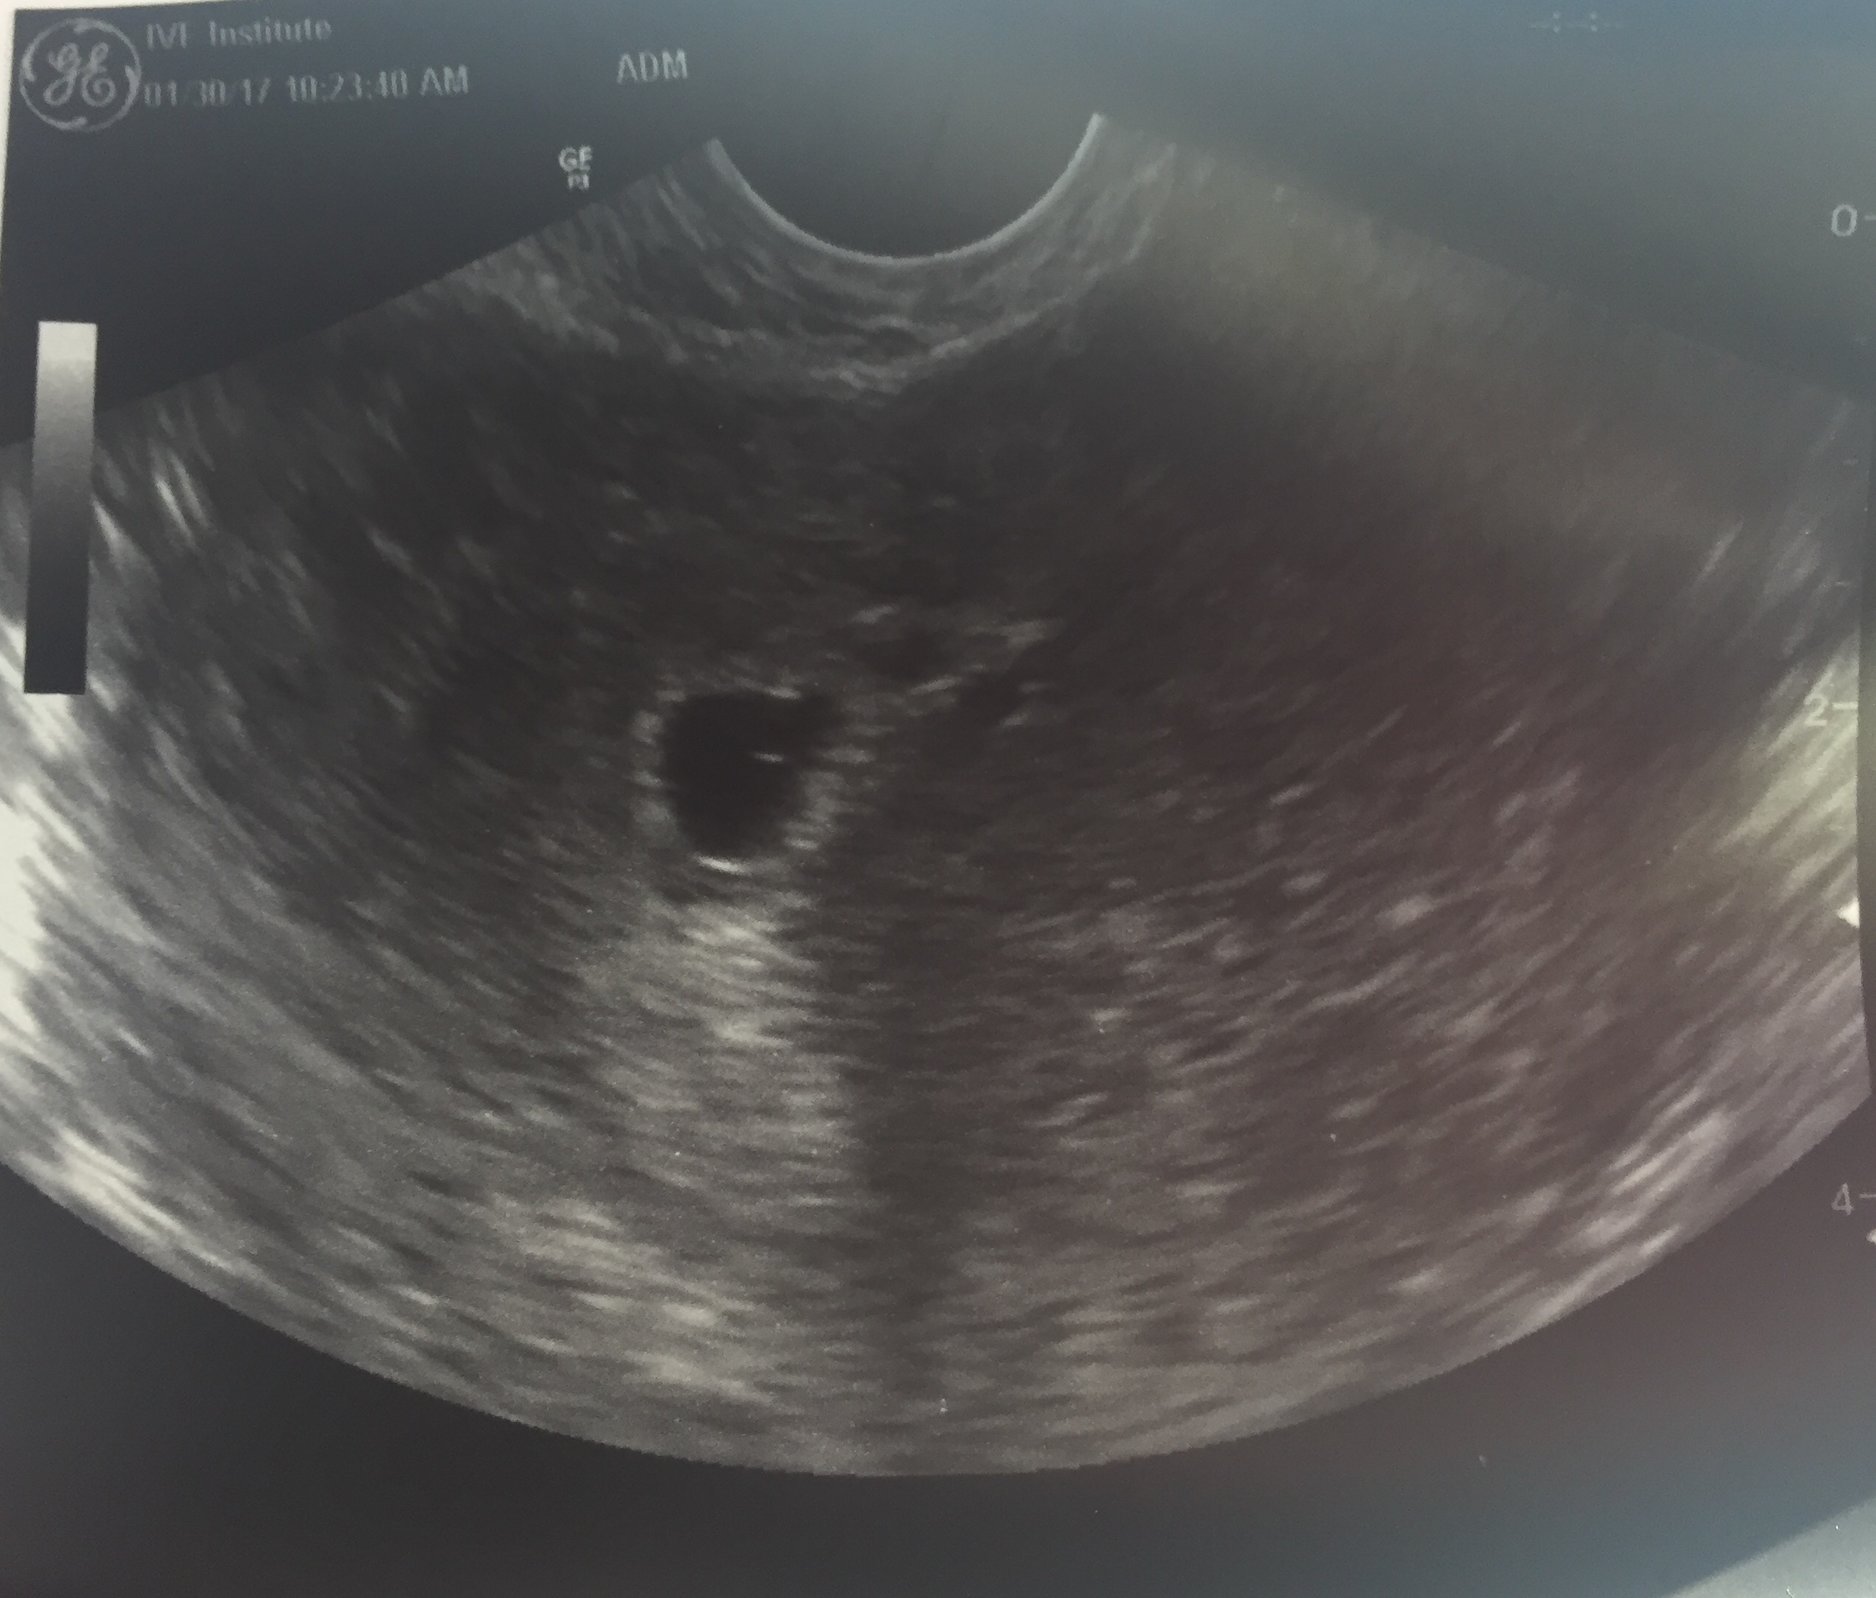

I'm 5W 3D and Just got out of Ultrasound #1 and there is 1 sac. so only 1 embie stuck. We go back on 2/10 to see the fetus and the heartbeat will be present by then! God is so good!

krisnjoe Awesome to get to see your little eggo! I hope your doing ok about it being a singleton. What an awesome picture! Looking forward to your 2/10 us!!

I'm 5W 3D and Just got out of Ultrasound #1 and there is 1 sac. so only 1 embie stuck. We go back on 2/10 to see the fetus and the heartbeat will be present by then!